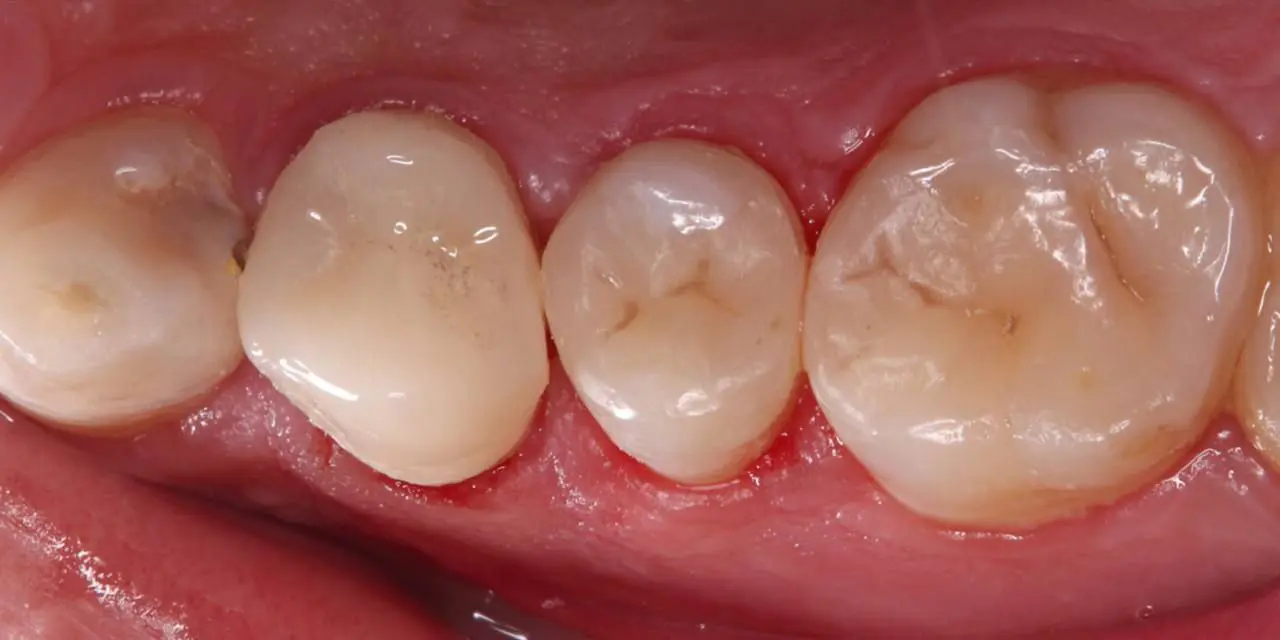

قبل

بعد